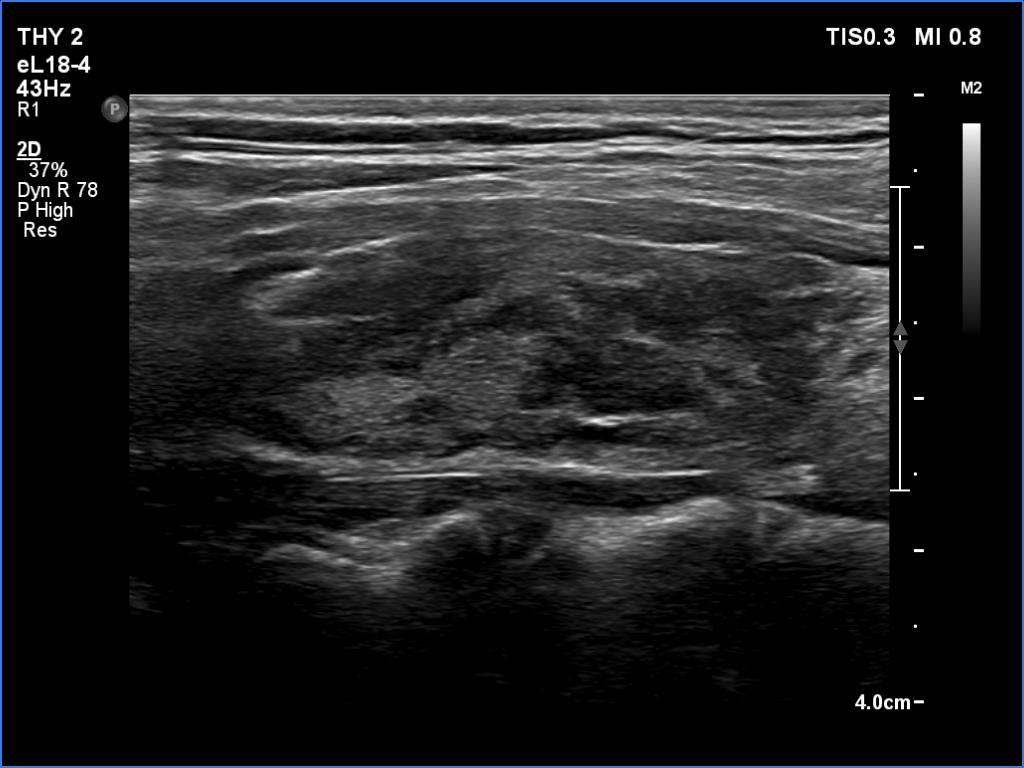

Ultrasonography. The thyroid was echonormal and had hypoechoic areas. The echogenicity index exceeded 50%. The pattern did not correspond to nodule. The vascularity was not specific.

Compared with the previous examinations, the ultrasound pattern remained unchanged.

Comment. This is the most common presentation of Hashimoto's thyroiditis, unfortunately not infrequently misinterpreted as a multinodular goiter. The multiplicity and the irregular borders of the discrete lesions are the main clues to avoid misinterpretation of these lesions as nodules.